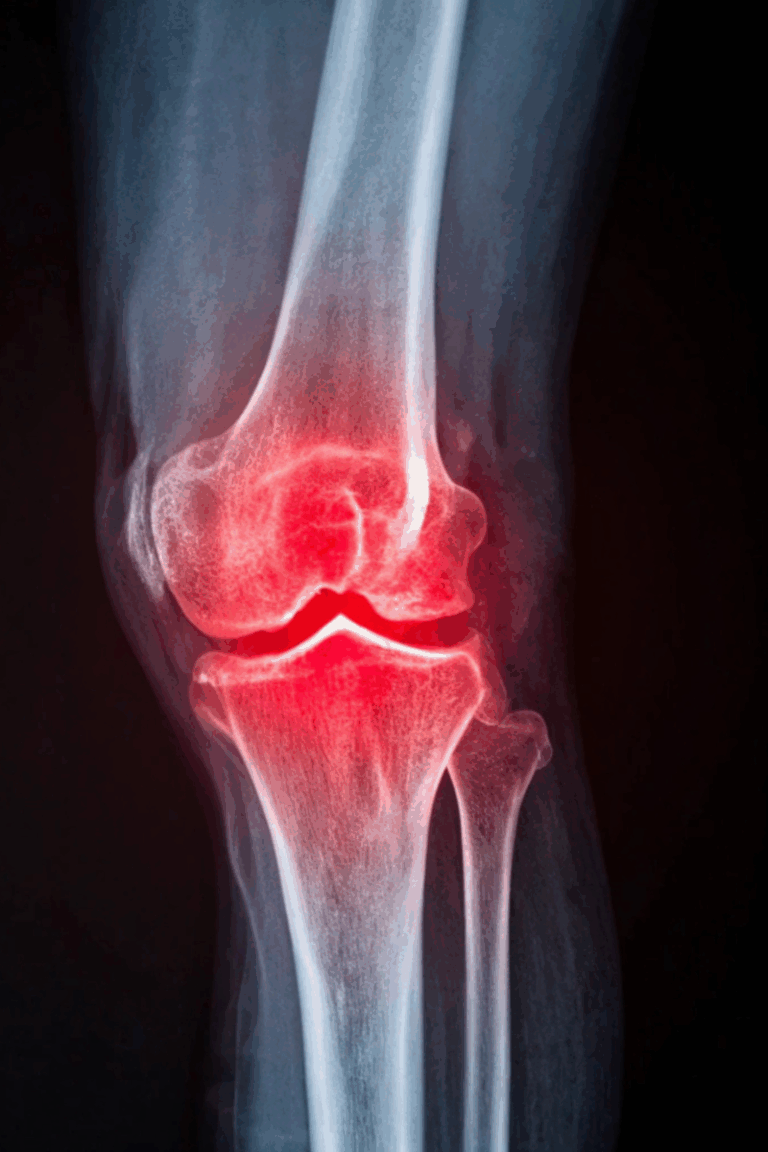

- Shoulder and knee injuries from awkward motions or accidents